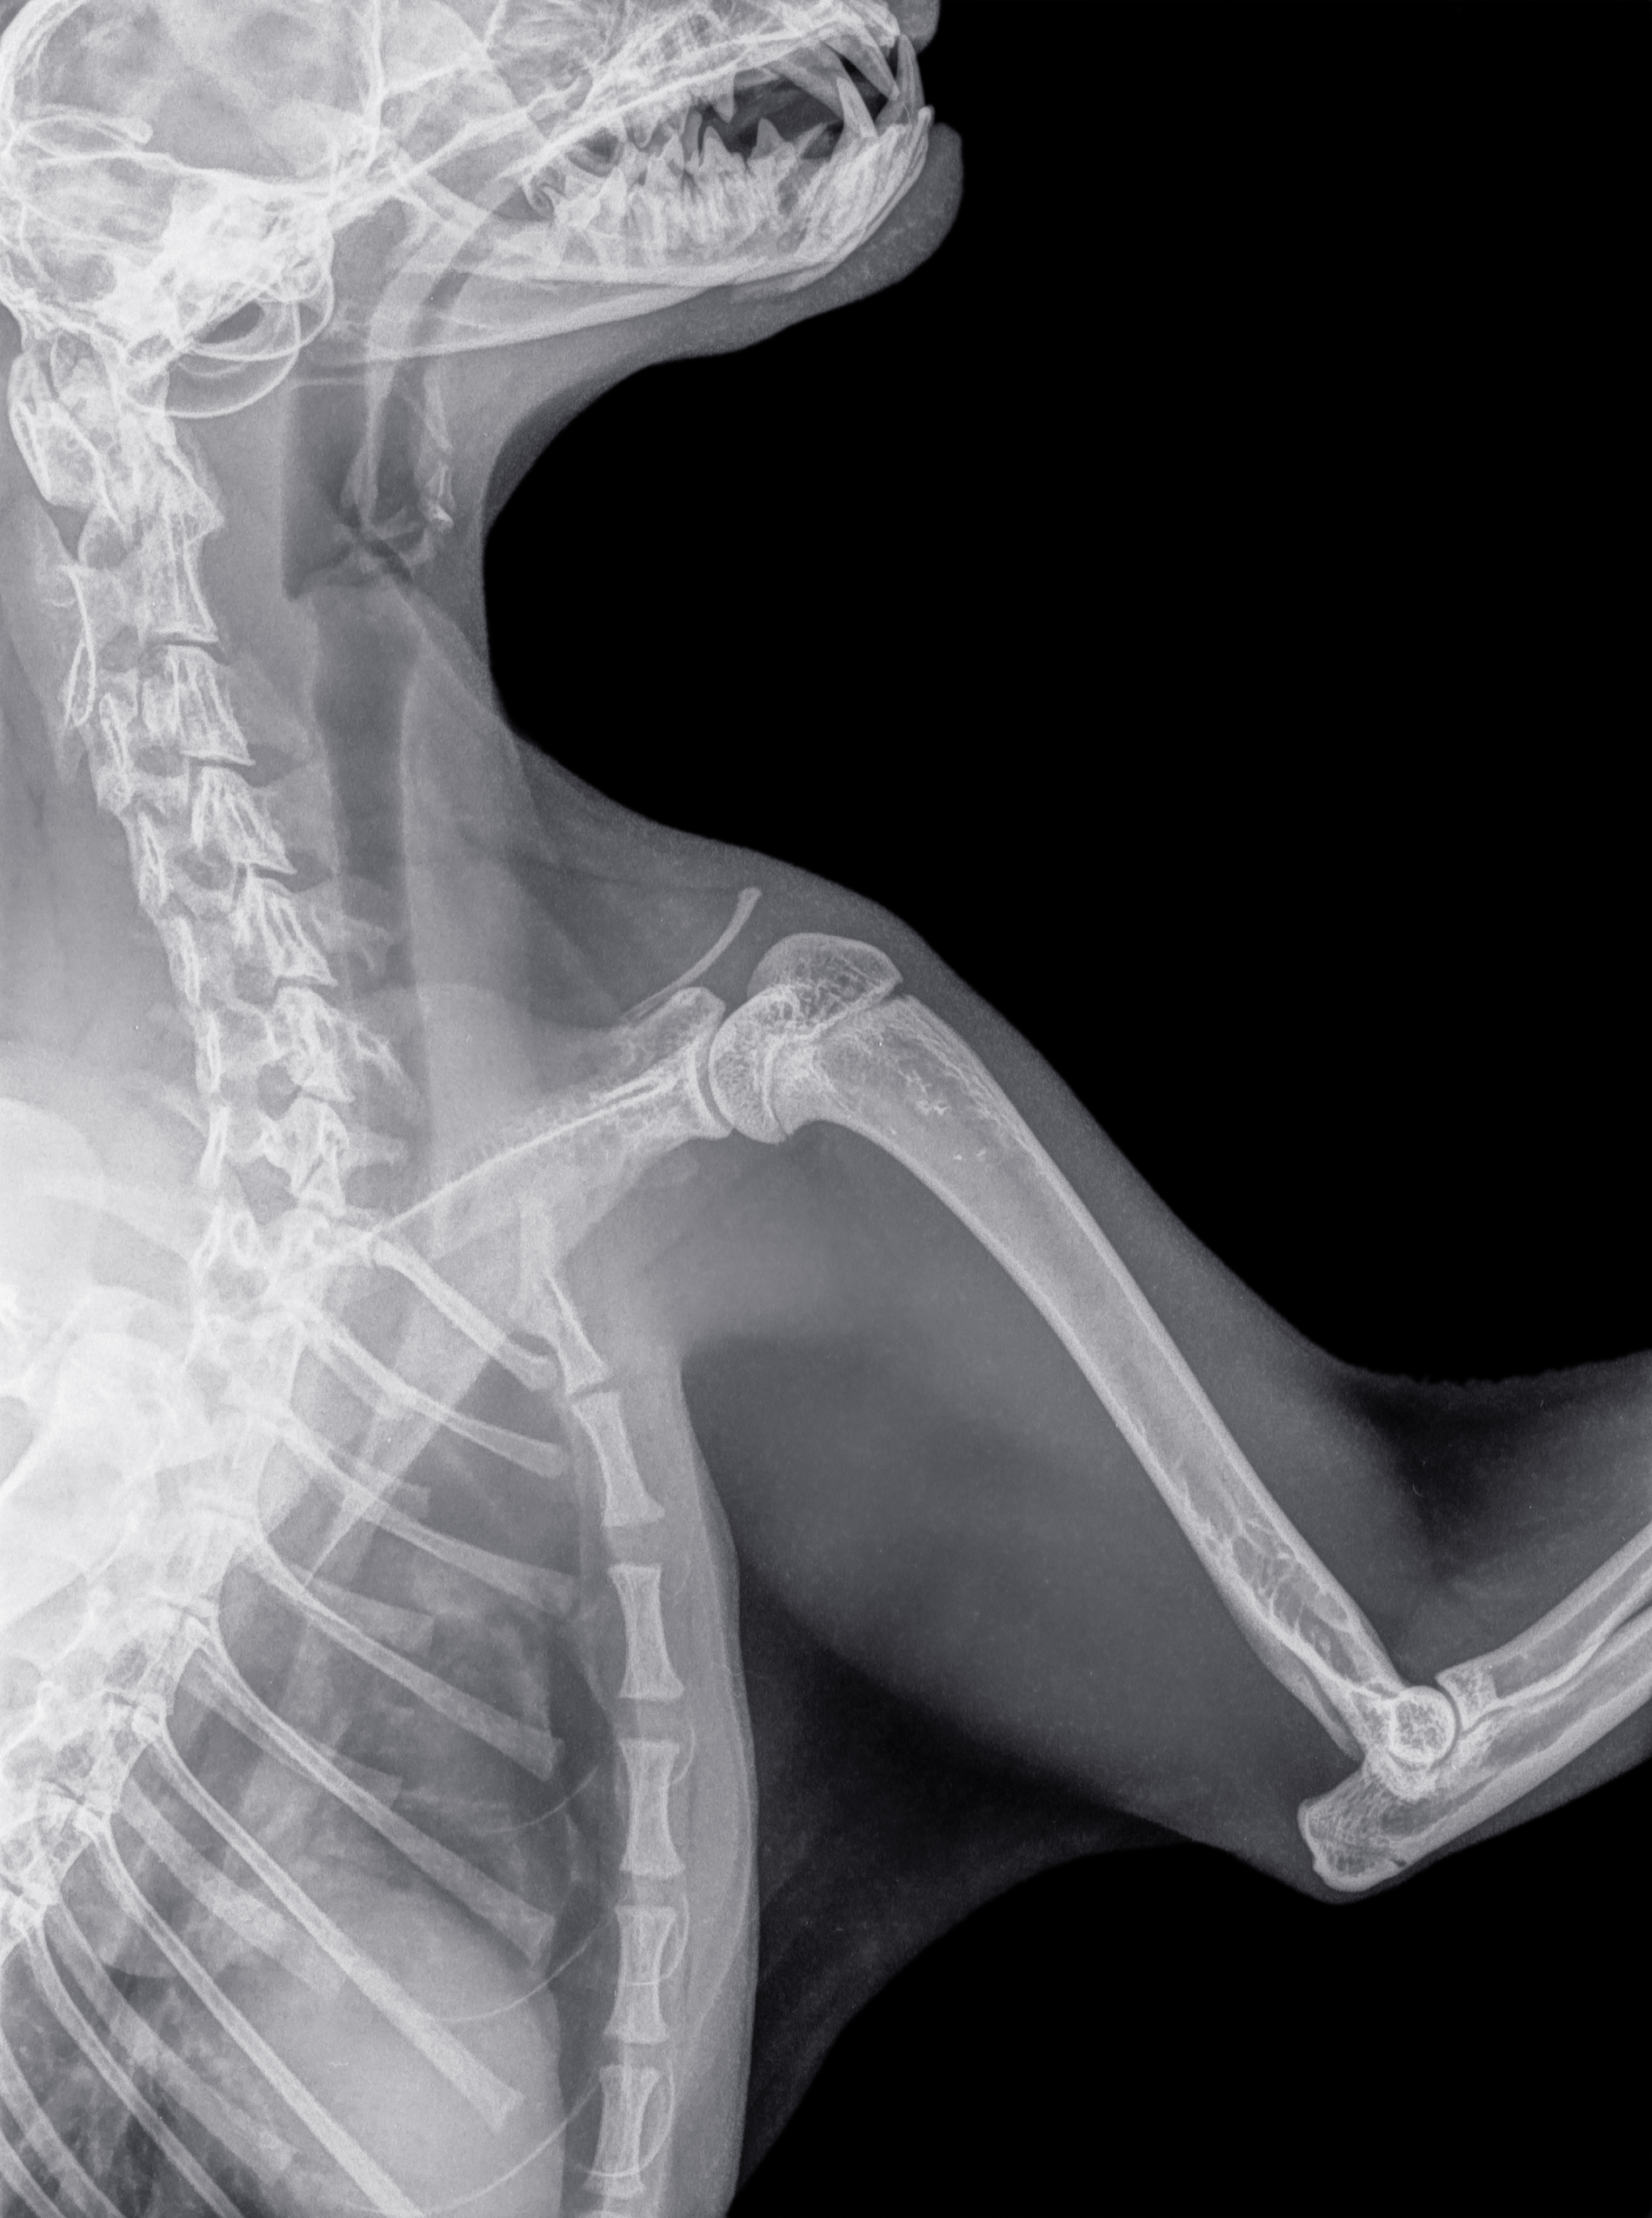

Screening requires a simple physical examination of dogs at least 12 months of age. A licensed veterinarian can take radiographs (x-rays) of both shoulders which will be reviewed by a radiologist at OFA. Dogs can be cleared, or be assessed as having unilateral OCD (one shoulder) or bilateral OCD (both shoulders).

The veterinarian will perform x-rays of your dog’s shoulders. Details about required positioning are outlined on the application form.